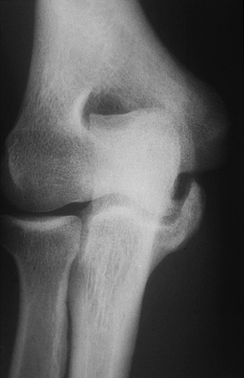

rather than of an acute injury to the ligament (Fig. 81.6).

Stress radiographs may reveal excessive laxity and medial joint line

opening, especially compared to the opposite elbow. In patients with

ulnar collateral ligament instability, radiographic valgus stress

testing may be used to document the degree of instability when the

diagnosis is in question. MRI may be used as an adjunctive diagnostic

tool, as it will clearly delineate pathology within the ulnar

collateral ligament (Fig. 81.8) (43).

with associated laxity. An MRI scan revealing a normal ulnar collateral

ligament (Fig. 81.7) can provide impetus to search for a different diagnosis. Arthrography is not useful

because of frequent false negative findings in cases of chronic ulnar collateral ligament insufficiency with an intact capsule.